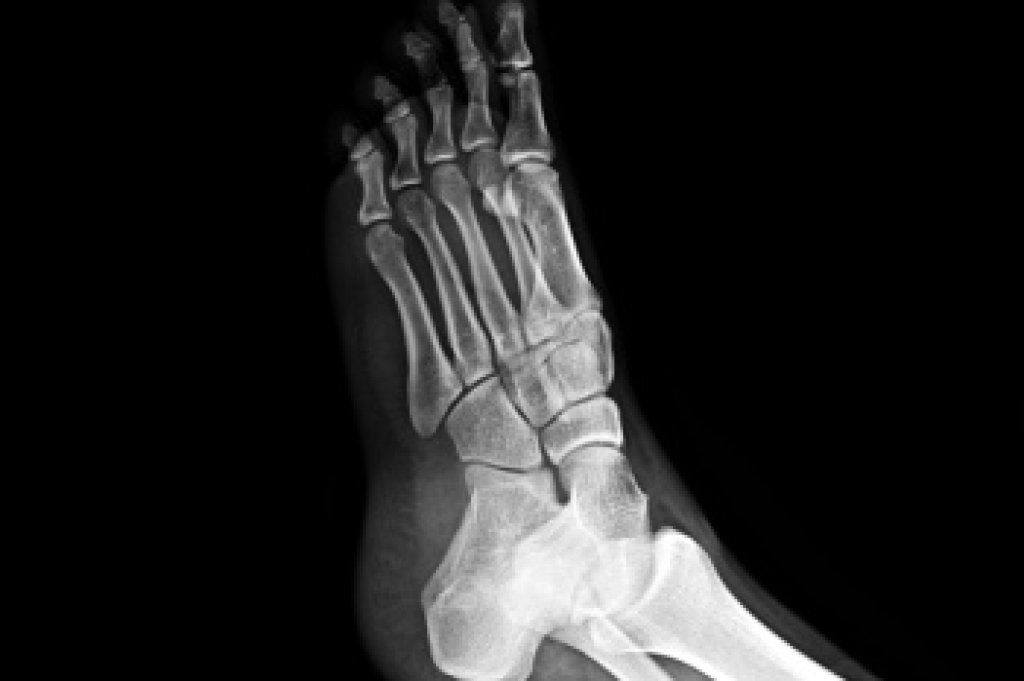

Plantar fasciitis is a common foot condition that causes pain in the heel and bottom of the foot. It occurs when the thick band of tissue along the sole of the foot, called the plantar fascia, becomes irritated or inflamed due to overuse, improper footwear, or excessive pressure. The hallmark symptom is sharp, stabbing pain in the heel, especially with the first steps in the morning, or after long periods of sitting. Treatment options include rest, stretching exercises, and anti-inflammatory medications. Wearing supportive shoes or using custom orthotics can also provide relief. In more severe cases, corticosteroid injections or even surgery may be necessary. A podiatrist can offer personalized advice, diagnose the condition, and recommend the best treatment plan. They can also help prevent future flare-ups by addressing underlying issues like improper gait or foot structure. If you are experiencing heel pain, it is suggested that you schedule an appointment with a podiatrist to get the care you need.

Plantar fasciitis is one of the most common causes of heel pain. The plantar fascia is a ligament that connects your heel to the front of your foot. When this ligament becomes inflamed, plantar fasciitis is the result. If you have plantar fasciitis you will have a stabbing pain that usually occurs with your first steps in the morning. As the day progresses and you walk around more, this pain will start to disappear, but it will return after long periods of standing or sitting.